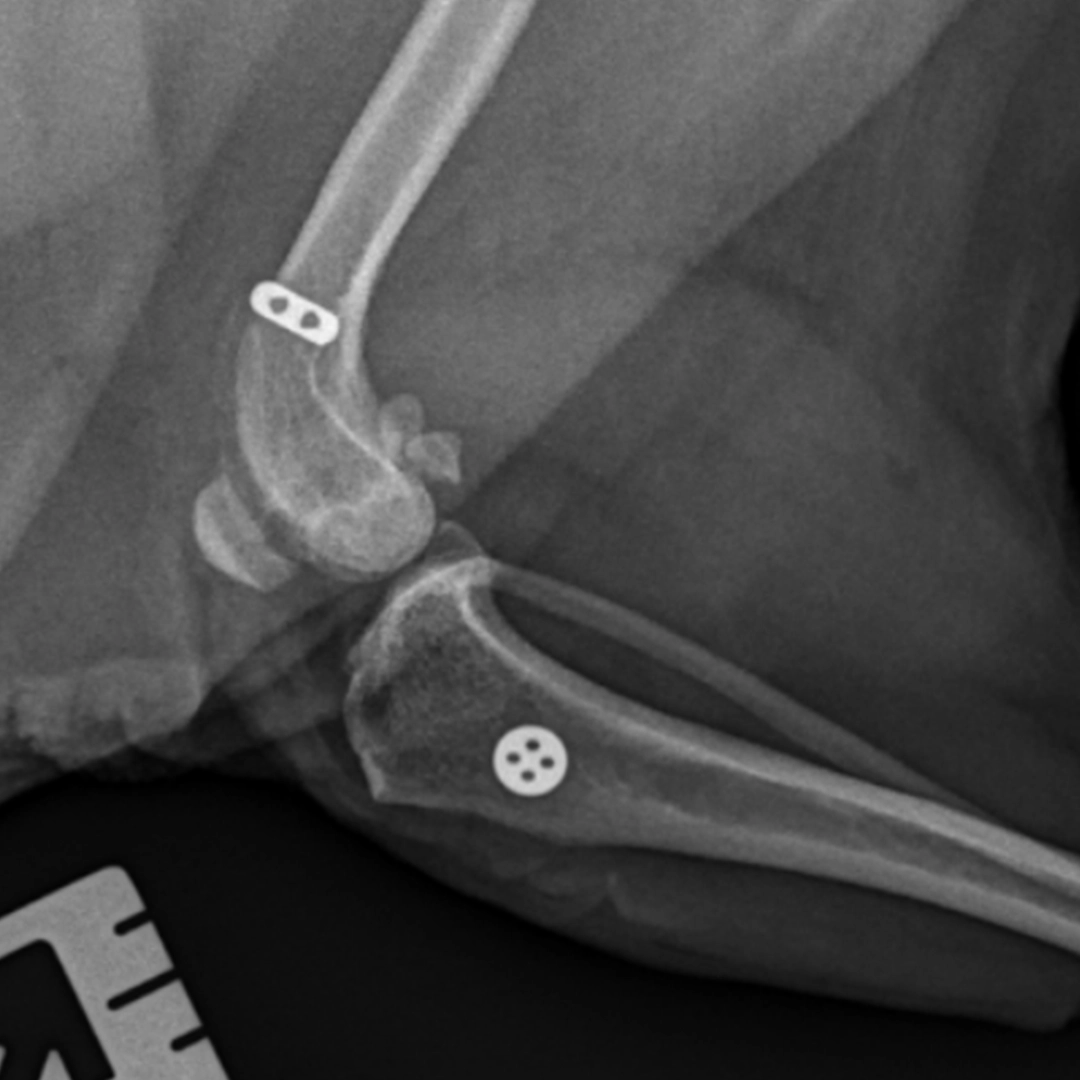

It involves implanting a prosthetic ligament, which can support 1000 lbs, 10 times more than any prosthetic ligaments used previously for veterinary medicine. The implant runs from the femur to the tibia through small holes and is held in place with small metal buttons on the outside. This replicates the function of the natural ligament, taking a large amount of strain off of the healing joint.